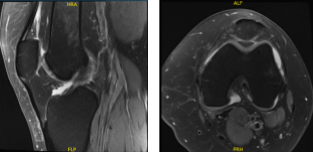

She was in the office with MRI results that showed complex multidirectional tear free edge lateral meniscus on the background of mild lateral compartment osteoarthritis. Mild patellofemoral compartment osteoarthritis as well.

MRI-3 Left knee non-contrast